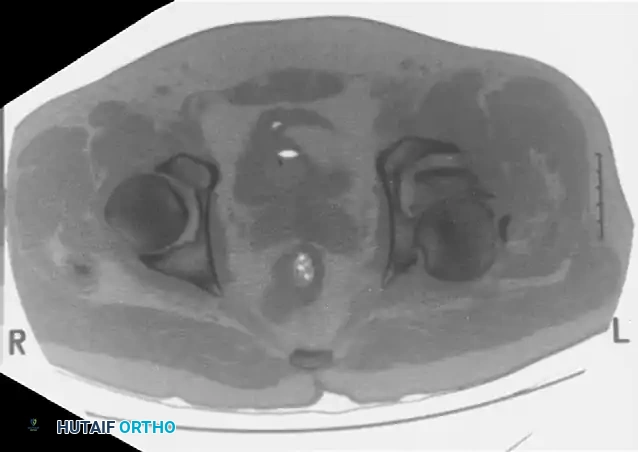

Computed Tomography (CT):

CT scanning is mandatory. It defines the size of wall fragments, the presence of intra-articular loose bodies, marginal impaction, and the exact orientation of fracture lines. CT is particularly critical in identifying incarcerated fragments that block closed reduction of a dislocated hip.